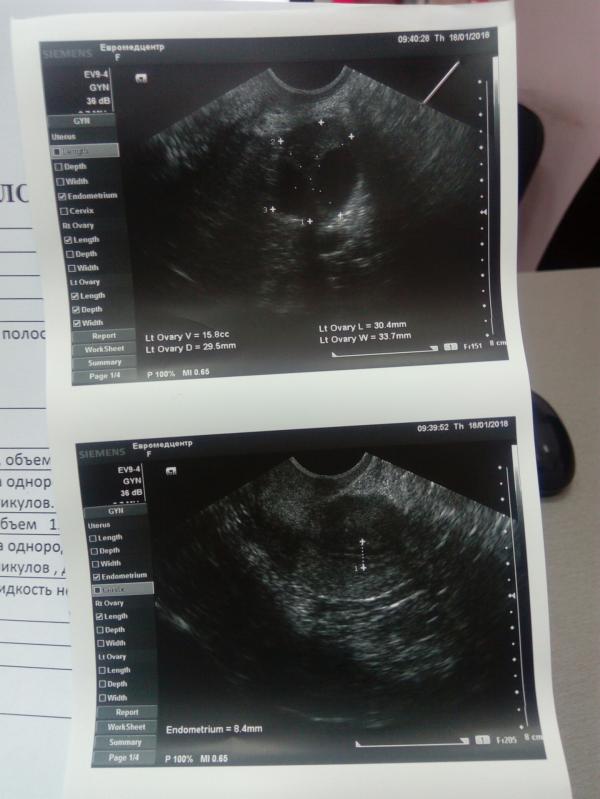

Хочу поделиться своей 3ей стимуляцией, до этого клостилбегитом стимулировались, сейчас Фемарой, и далее андрогель, итог: сегодня 16ый день цикла, овуляции еще не было, так как цикл у меня по 32± дней, созревших два фолликула, 20.5 и 21, мм(на 13день цикла так же было два доминантных по 13.3 и 13.7мм, эндометрий подрос до 8.4мм, был 5.3, в общем ощущение в левом боку потягивает, видимо из-за того, что скоро овуляция! В общем я была бы счастлива если бы произошло зачатие двоих моих фолликов, надеюсь на чудо)))